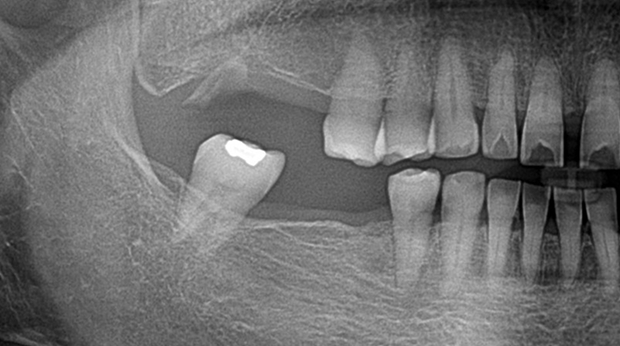

매복 사랑니 발치

임플란트와 사랑니 발치는 외과적 시술로 잇몸을 절개하는 외과적 시술은

짧으면 짧을 수록 시술 후 붓기와 통증이 최소화됩니다.

치과의사 경력 14년차 구강외과 전문의가 빠르고 안전하게, 아프지 않게 수술해 드립니다.